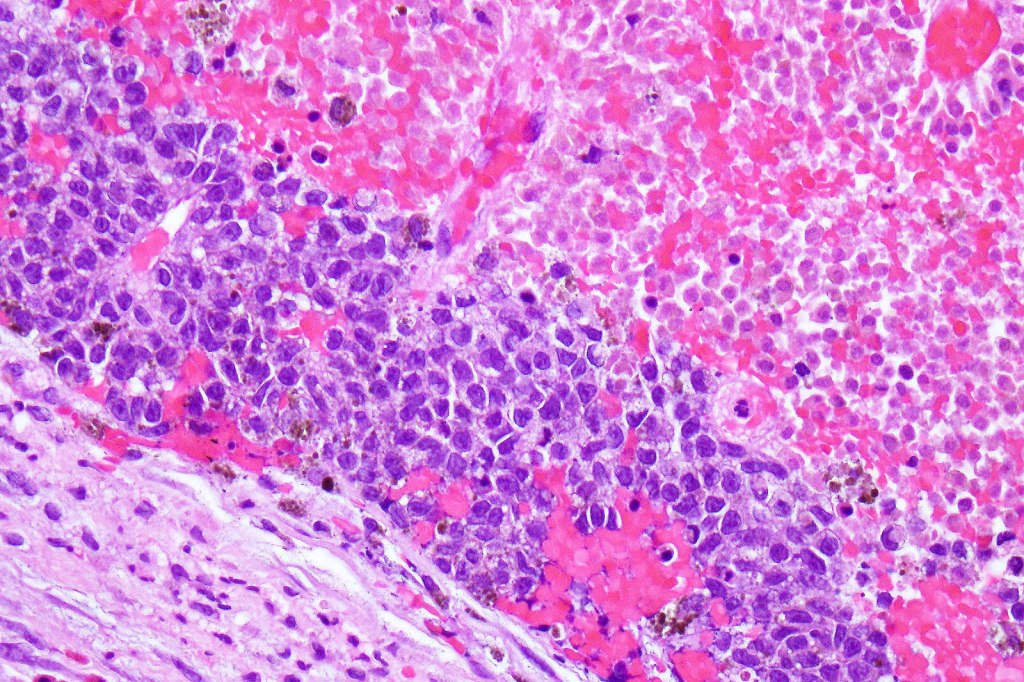

•Develop in the dermal component

•Typical melanoma, nevoid melanoma, small cell melanoma, pleomorphic/anaplastic melanoma, melanoma with heterologous differentiation & malignant nerve sheath-like melanoma.

This melanoma arose in a small congenital nevus of the scalp. It metastasized widely. Varying features in different fields.